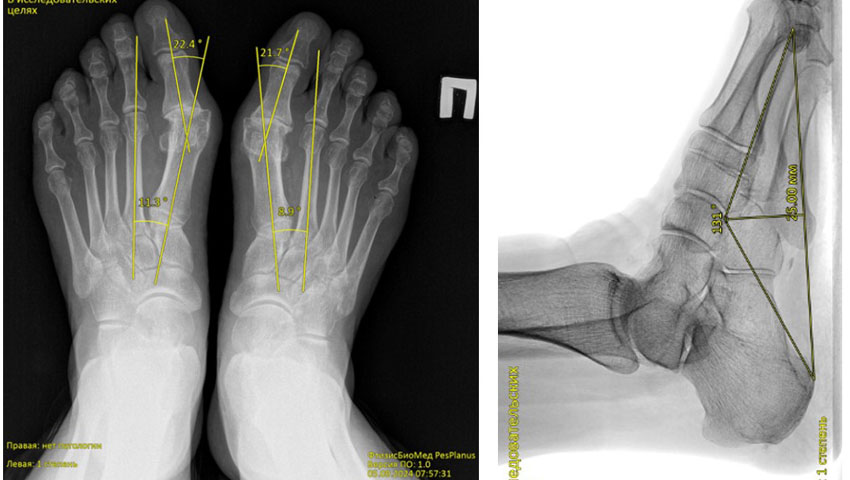

Chương trình phân tích tự động ảnh ‘X-quang bàn chân’ phát hiện bàn chân bẹt dọc và bẹt ngang

FtizisBioMed PesPlanus được phát triển nhằm phân tích tự động hình ảnh X-quang kỹ thuật số của bàn chân, hỗ trợ bác sĩ trong việc:

Phát hiện sớm các dấu hiệu bàn chân bẹt dọc và bẹt ngang;

Giải pháp công nghệ

Chương trình ứng dụng trí tuệ nhân tạo y tế (Medical AI) và các mô hình học máy tiên tiến để phân tích hình ảnh X-quang bàn chân. Hệ thống được huấn luyện trên tập dữ liệu lớn đã được gán nhãn bởi các chuyên gia đầu ngành, đảm bảo độ tin cậy và khả năng tái lập kết quả cao.